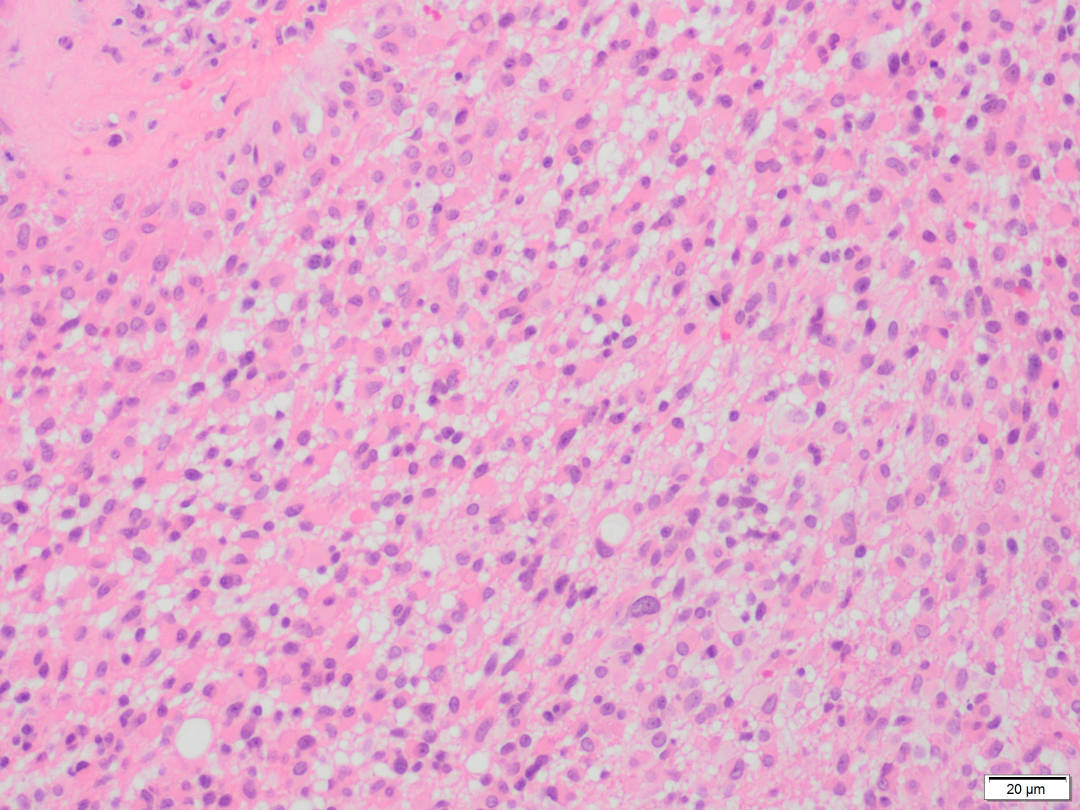

NEUROPATOLOGÍA.

Nuestros especímenes quirúrgicos incluyen las biopsias de pacientes con neoplasias del sistema nervioso central y periférico, enfermedades infecciosas, inflamatorias y degenerativas.